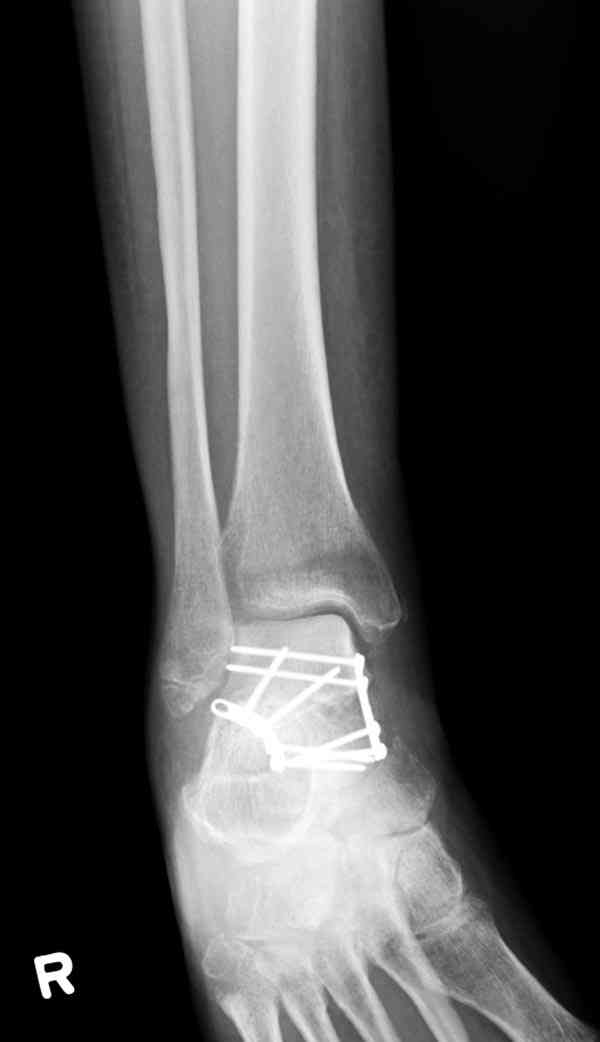

Случай с множественным оскольчатым переломом тарана оперированный из двойного доступа.

Через 2 мес.:

Через 8 мес.:

Через 14 мес.:

Из-за отсутствия времени пришлось оперировать на второе утро, из материала, что имеем на месте, фиксирован двумя шурупами, а третий-это контур сломанного жойстика в 4 мм. На дистальный медиальный конец тибиа antiglide 3.5 мм пластина. Через пару дней выписан и несмотря на предупреждение, самостоятельно начал нагрузку в 4 недели, время не ждет, снимается в боевике в Росийской Федерации.